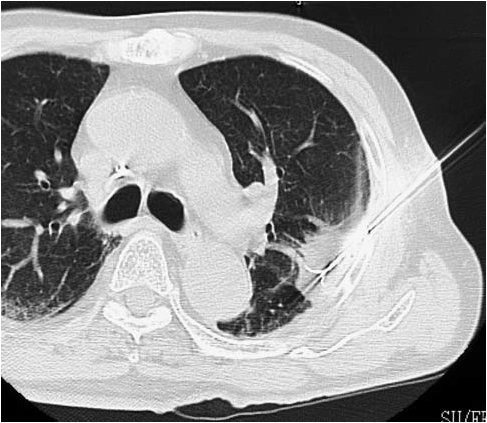

Image-guided cancer ablation is a minimally invasive, non-surgical treatment used to destroy selected cancers by precisely delivering heat energy directly into the tumour under real-time imaging guidance such as ultrasound or CT.

Image-guided cancer ablation is a minimally invasive, non-surgical procedure that destroys selected tumours by delivering controlled heat directly into the cancer using real-time imaging such as ultrasound or CT.

Ablation is commonly used for selected liver, kidney, lung, and bone tumours, as well as certain benign tumours causing symptoms. Not all cancers are suitable, and careful evaluation is essential.

- Lung cancer